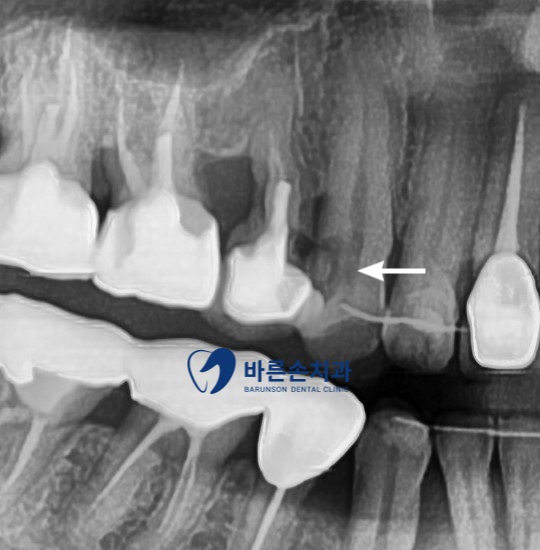

이런 경우 육안 상으로는 큰 문제가 안 보이지만 엑스레이 판독 결과

충치가 치아 신경까지 있는게 보이네요

이렇듯 육안 상으로는 안 보이는 충치도 엑스레이를 통해 확인 할 수 있고

몇 회에 걸쳐 신경치료를 한 후 엑스레이 촬영 결과 치아의 뿌리 끝까지 신경치료 잘 마무리 되었고